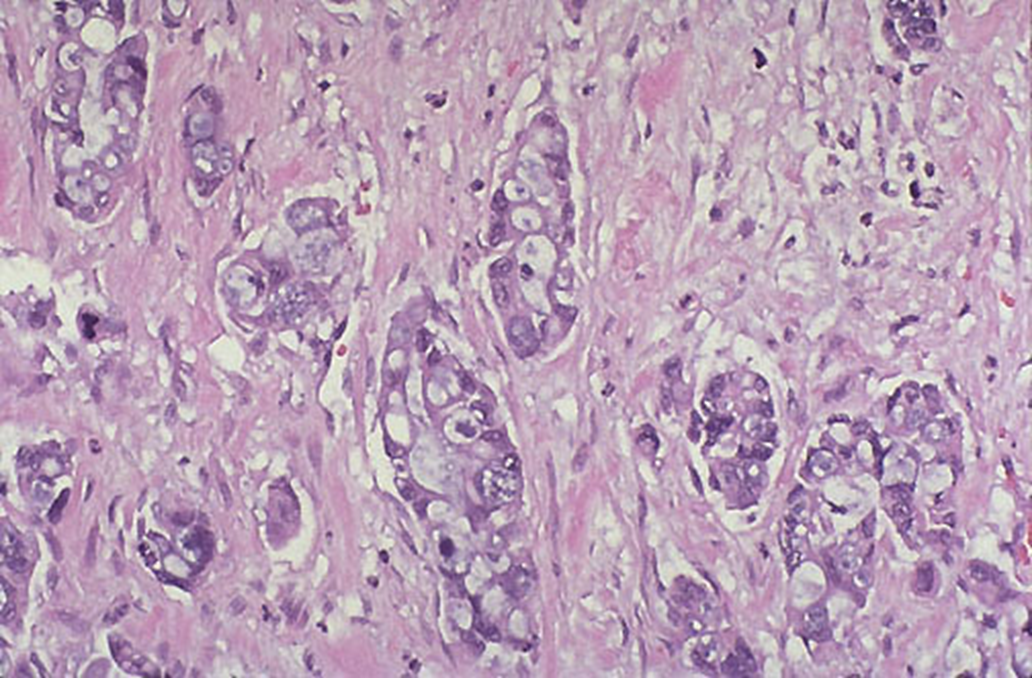

panc adenocarcinoma.

poorly differentiated glands and extensive desmoplasia (collagenous stroma)

pancreatic adenocarcinoma